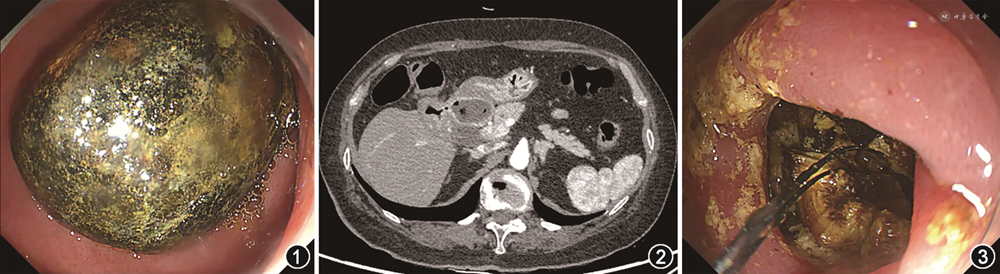

经过禁食、胃肠减压、抑制胃酸及营养支持等初步处理后,患者在入院第5天接受了第2次胃镜检查,在患者的十二指肠球部发现了一枚直径约2 cm的圆球形异物(图1)。初步诊断胃出口梗阻。随后进行CT检查,提示十二指肠球部异物,球部外侧局部与胆囊相通,考虑胆囊十二指肠瘘,另可见胆囊壁增厚与胃黏膜、小肠局部肠壁黏膜强化,考虑炎症(图2)。判断结石正是通过瘘管从胆囊进入肠道。

这例患者最终被确诊为Bouveret综合征。考虑到患者的一般情况和结石的尺寸,与肝胆外科及患者家属讨论后决定为其施行内镜下的钛激光碎石术。在全身麻醉插管后进镜至胃腔,予钛激光反复碎石,最终将结石分为数块后以网篮及异物钳经口腔取出,复观察球部,可见球降狭窄,勉强通过胃镜,而后于球部后壁发现一处充血水肿的瘘口。手术全程约1 h,未见周围组织损伤(图3)。由于内镜技术的局限性,瘘管无法得以修复。患者术后无不适主诉,静脉用盐酸莫西沙星及吗啉硝唑3 d预防感染,其余予抑制胃酸、止血、营养支持等治疗。术后第4天行腹部磁共振成像回报:十二指肠取石术后改变,胆囊十二指肠球部瘘,术区少量积液,可见渗出性改变,胆囊结石可能。对比前片,暂无特殊干预,嘱患者密切随访,建议患者出院后至肝胆外科就诊以评估是否需手术切除胆囊,患者由于个人原因暂不考虑手术。患者对治疗效果十分满意,于术后第6天顺利出院,至今状态良好,未见疾病复发。